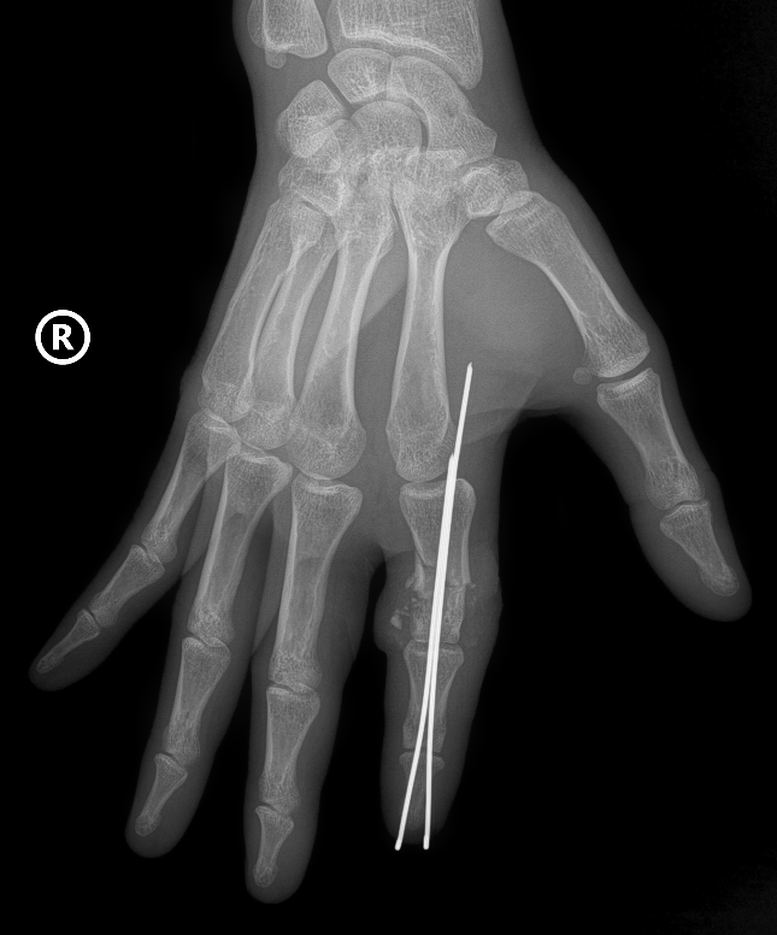

A beteg levágott ujjának megtalálása és rögzítése egy speciális tűvel - Fotó: VGP

Az ujjcsontot egy speciális tűvel rögzítik és helyezik el, hogy stabil tengelyt hozzanak létre, az ín- és szalagrendszert pedig helyreállítják. Különösen az idegeket és az apró, mindössze 0,8-1 mm-es ereket állítják helyre nagy pontossággal sebészeti mikroszkóp alatt, speciális eszközökkel, hogy biztosítsák a vérkeringés helyreállítását az elvágott részben.